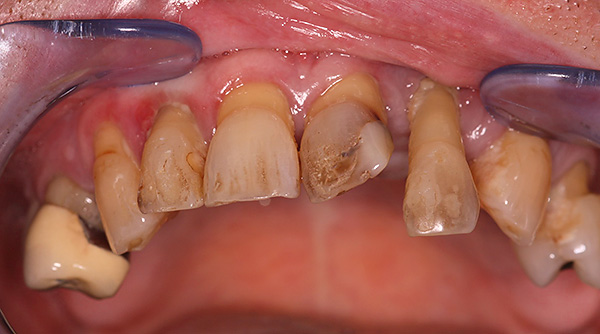

Le fotografie seguenti mostrano un esempio di impianto di un dente anteriore appena rimosso (che si è rotto da una lesione meccanica):

nota

In alcune situazioni, quando le condizioni del tessuto osseo lo consentono e l'impianto ha una fissazione primaria abbastanza buona, è possibile installare una corona in metallo-plastica economica per il periodo di osteointegrazione dell'impianto. Per i denti anteriori, questo è particolarmente importante, poiché consente di ripristinare l'estetica della dentatura in modalità express. Considerando che i denti anteriori non sono coinvolti nella masticazione del cibo, il carico sull'impianto sarà minimo.